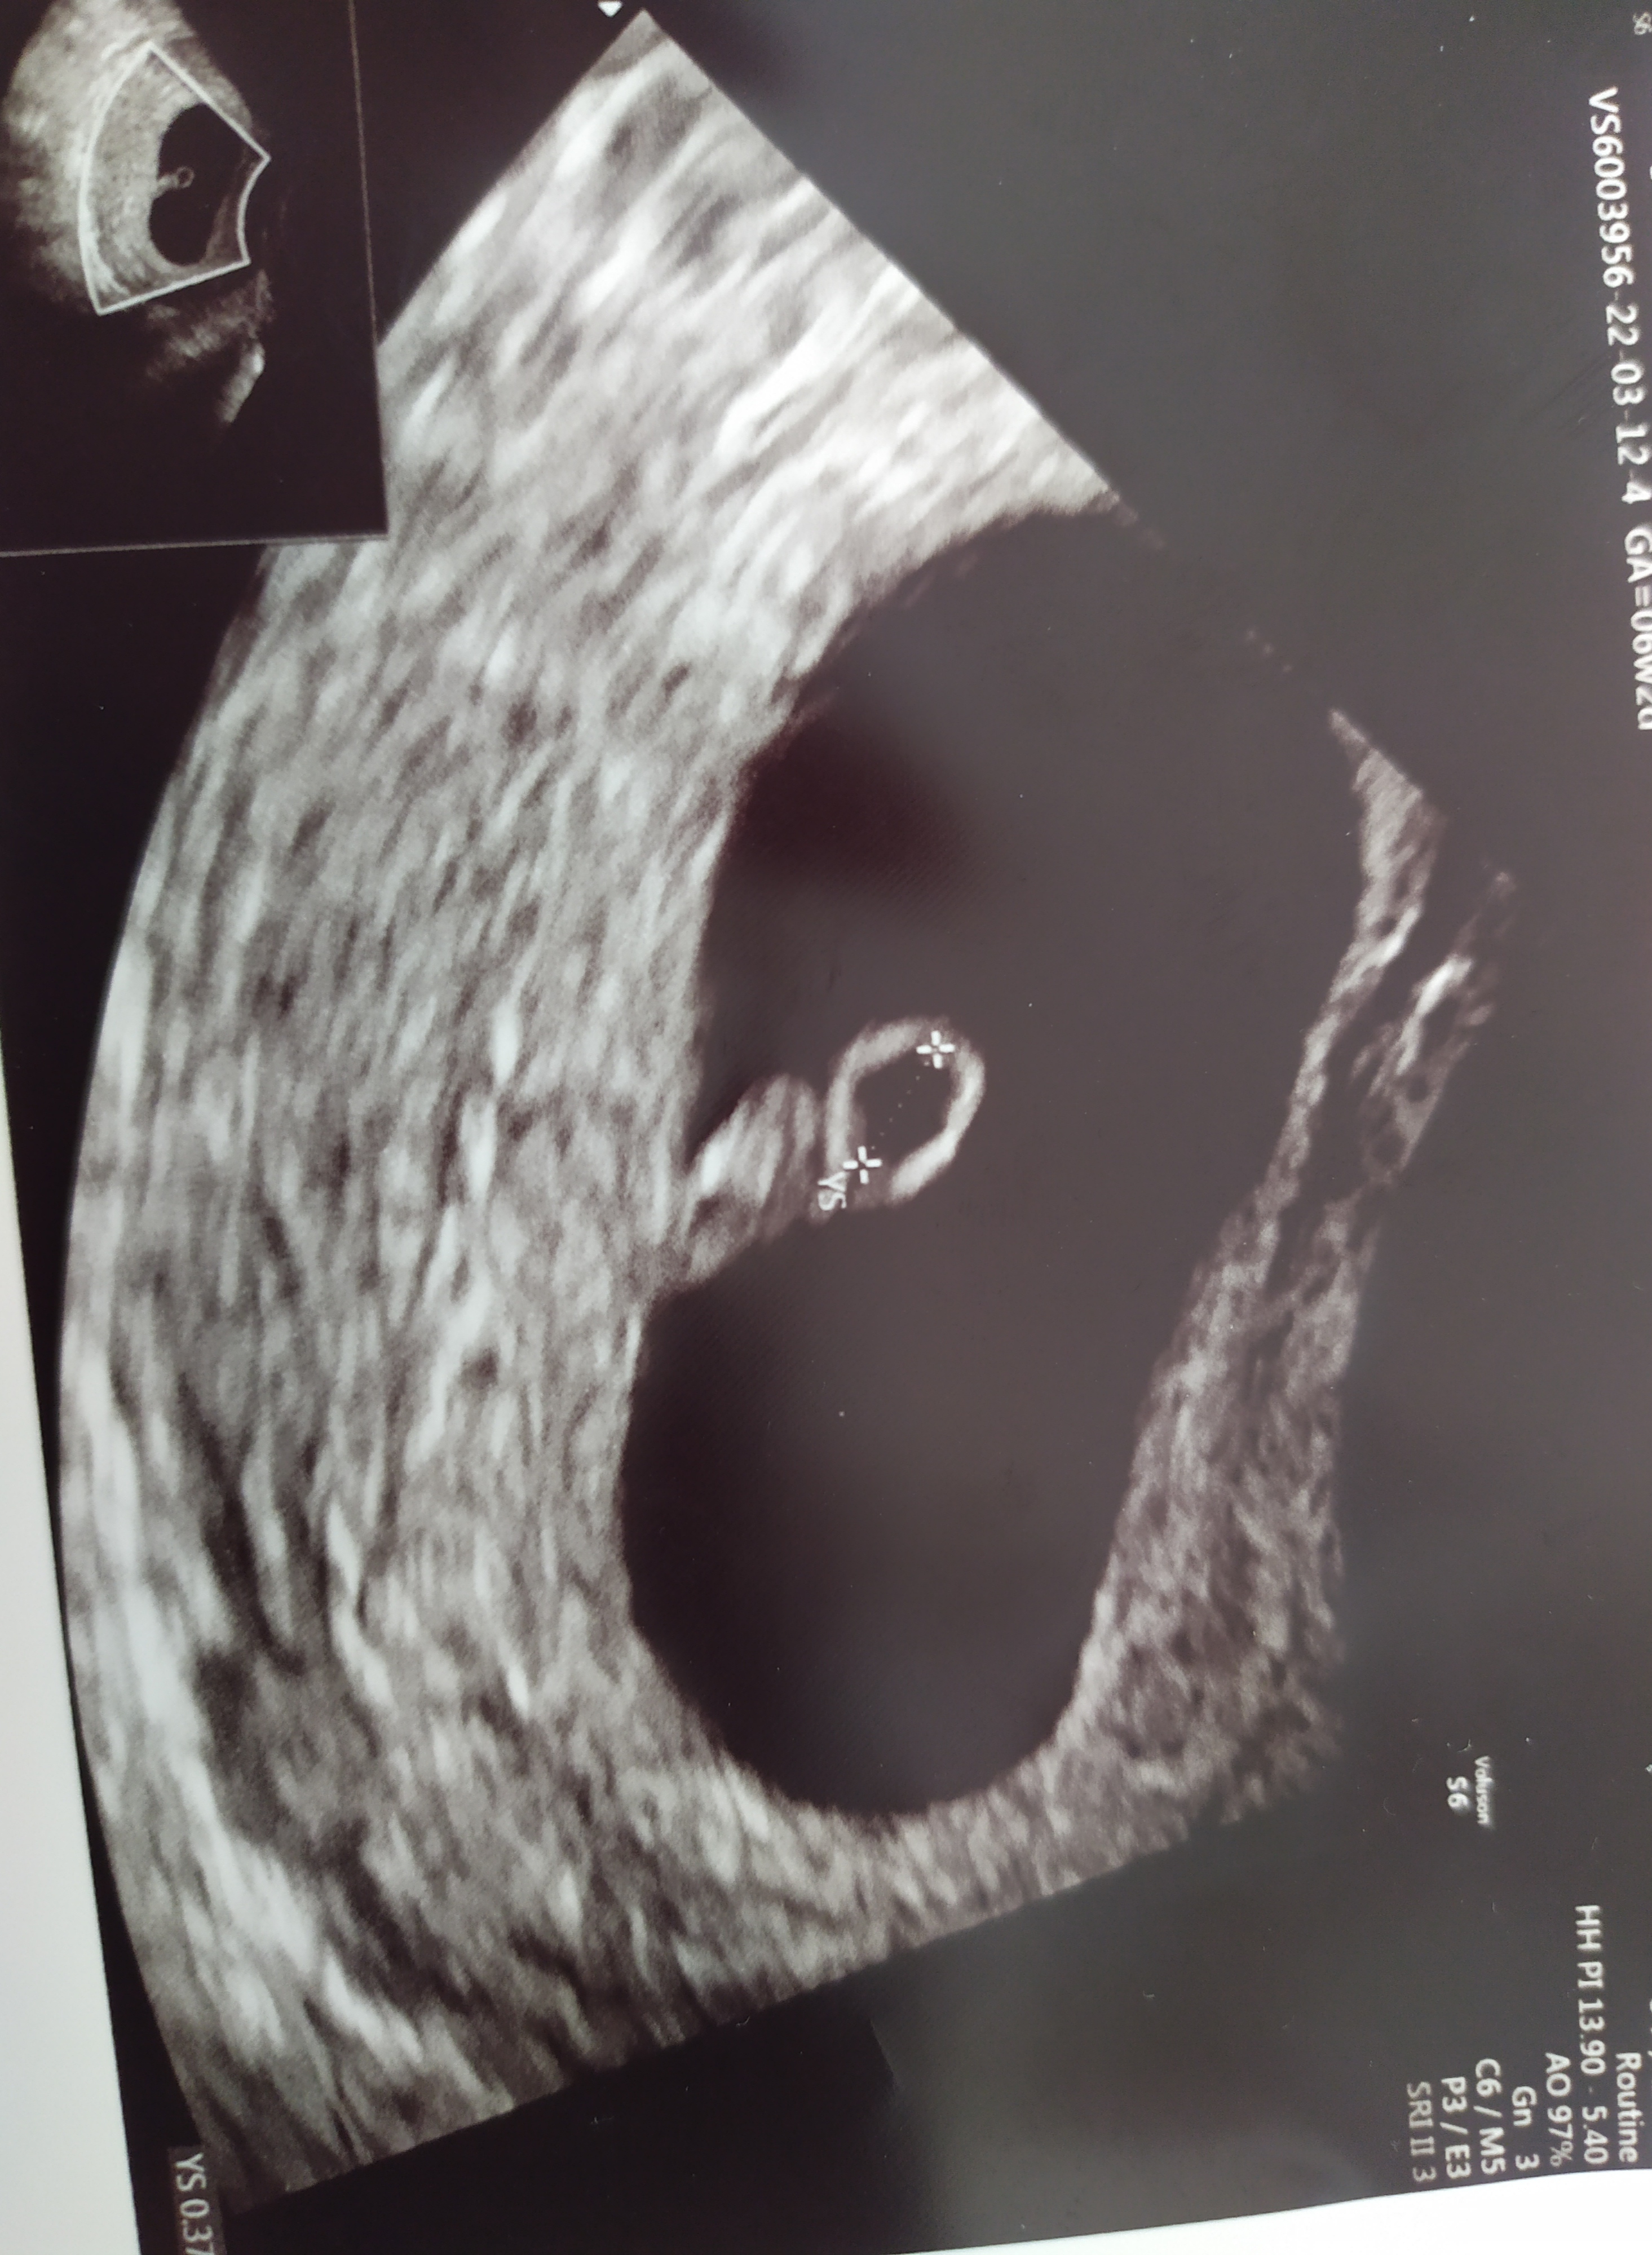

Ben pek bir şey goremedim başka daha net bir görsel var mı?